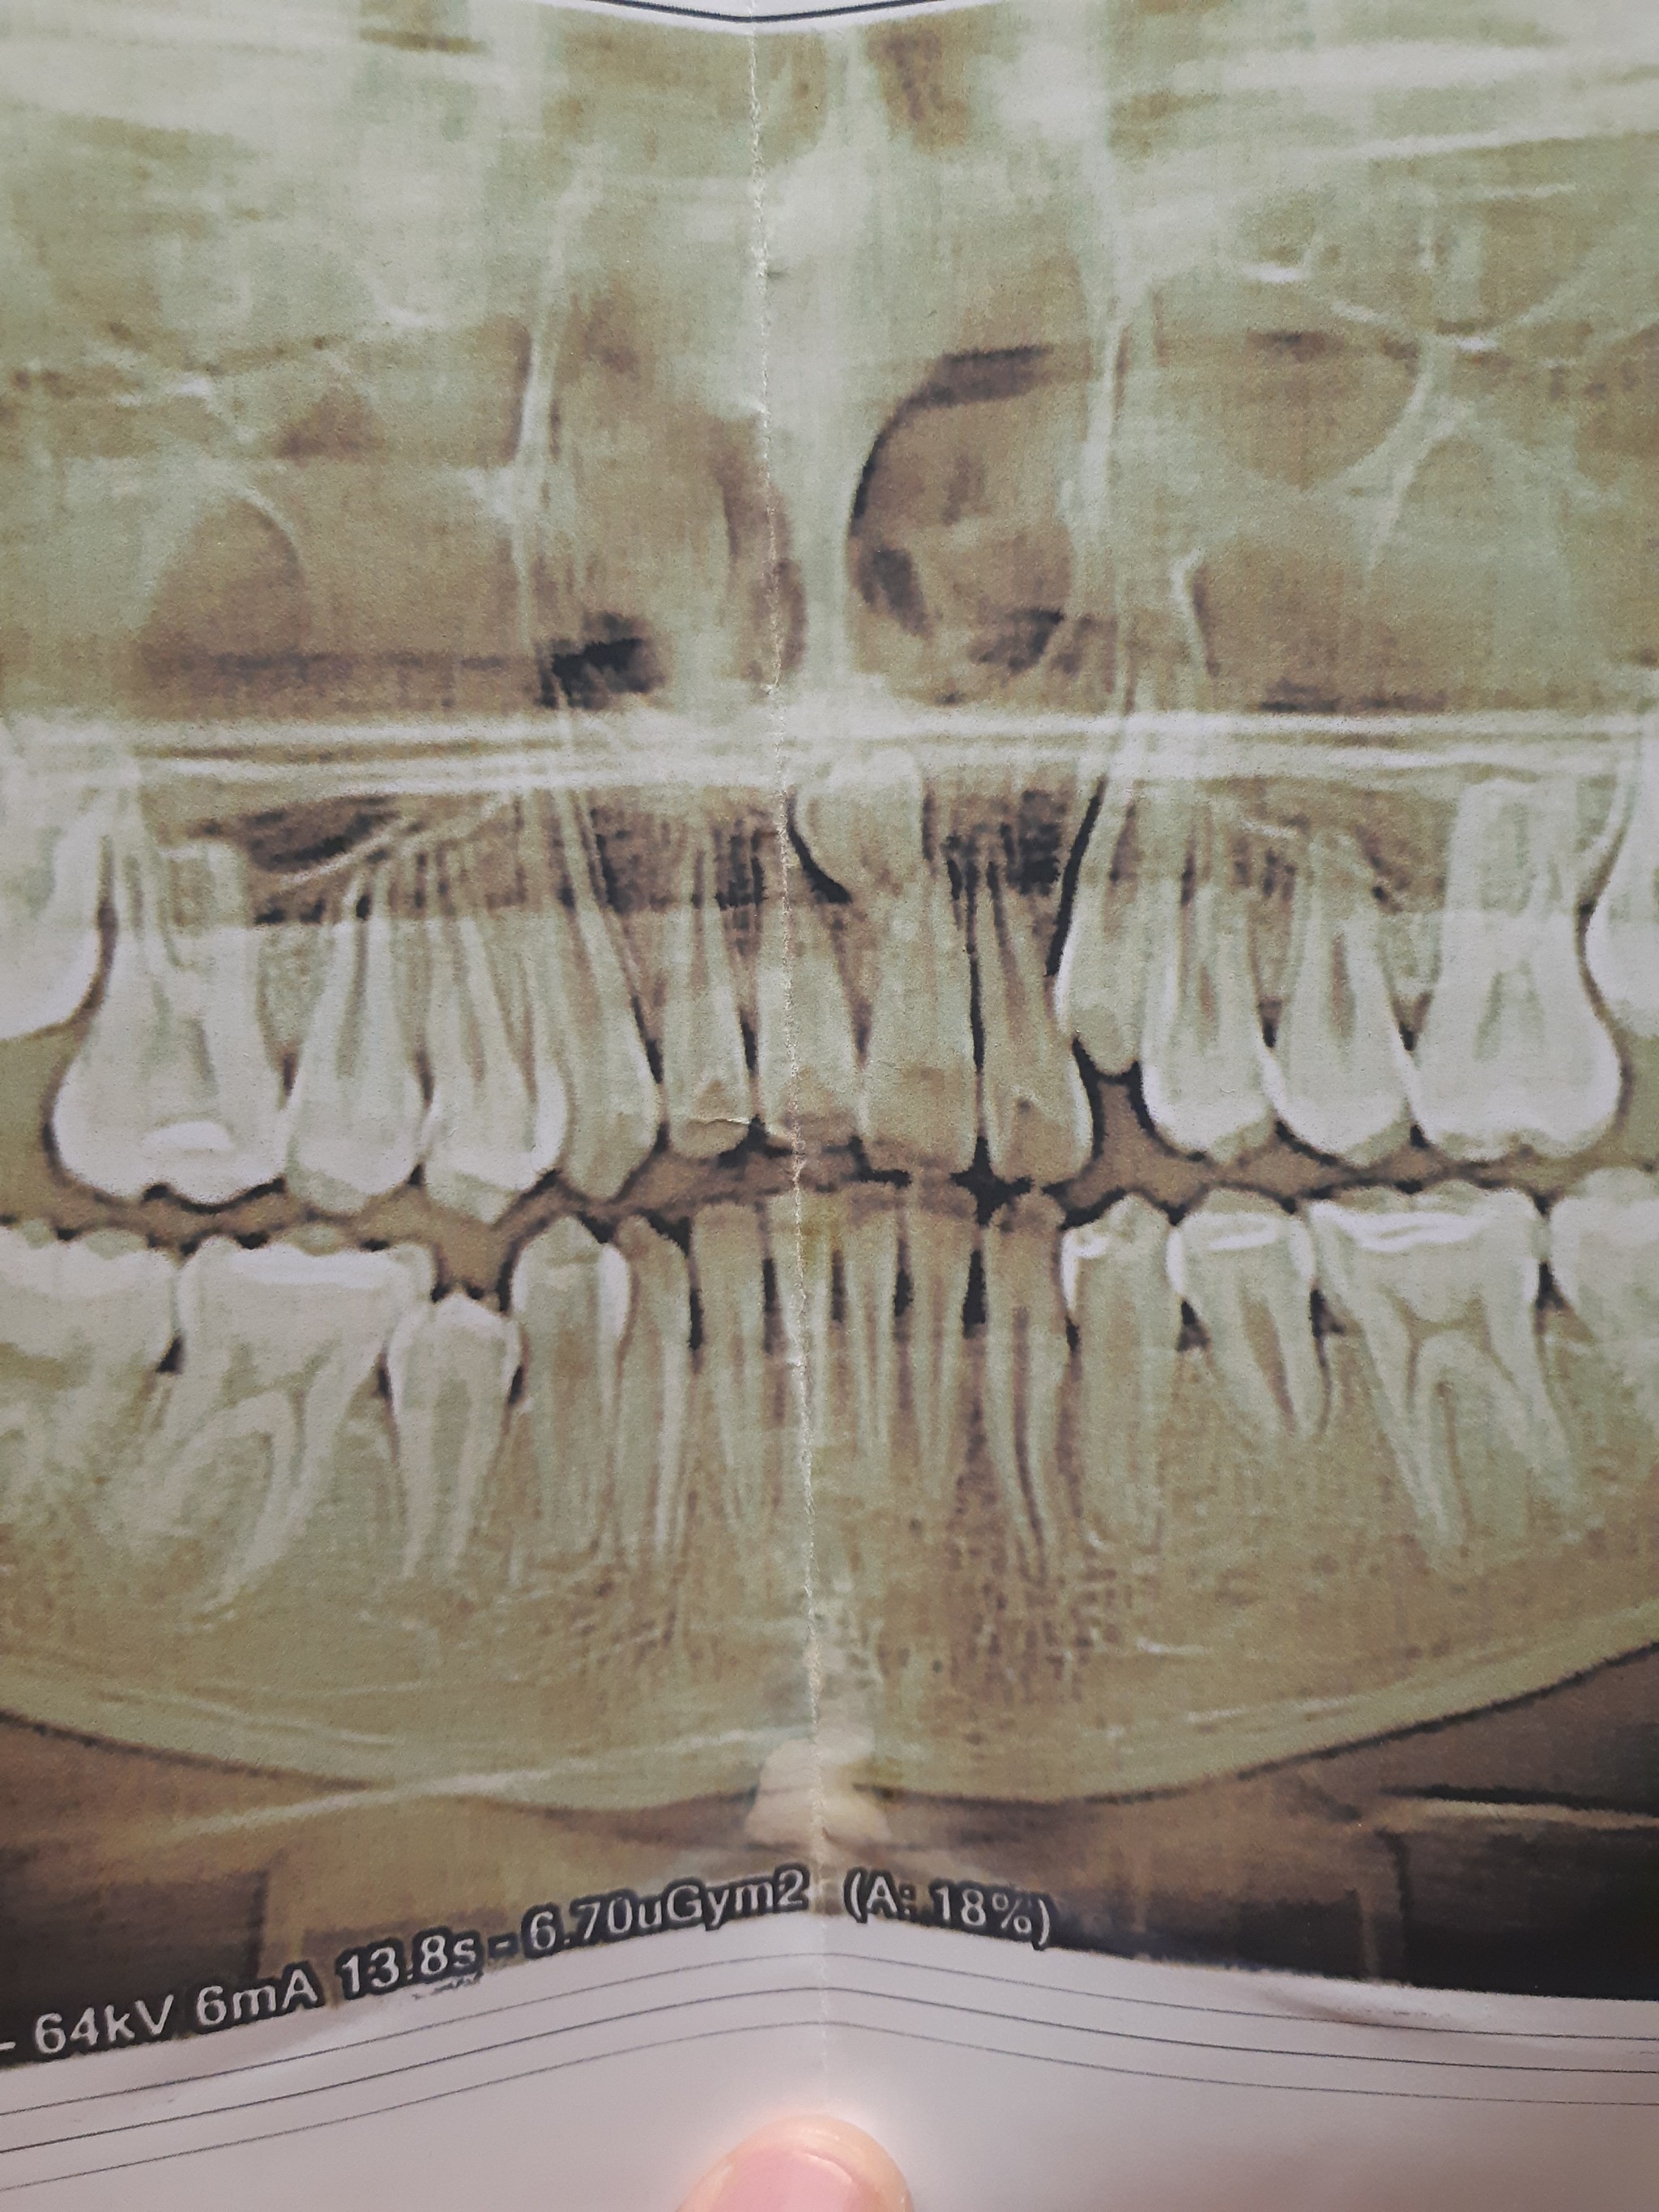

Снимок ниже сделан сразу после операции.

Дальше задача наблюдать и ждать, пока костная ткань в этой области восстановится.

После удаления было проведено несколько осмотров, снятие швов – все как обычно. Через месяц – контрольный снимок.

Что мы видим? Темное пятно в области проведенной операции сохраняется, что нормально, потому как прошел всего месяц с момента удаления. Заживление проходит хорошо, каких-либо проблем в восстановлении не наблюдается. Не зря я отметил пунктиром область зуба мудрости с противоположной стороны, потому как там есть точно такая же фолликулярная киста, как и слева, но на начальных этапах своего роста.